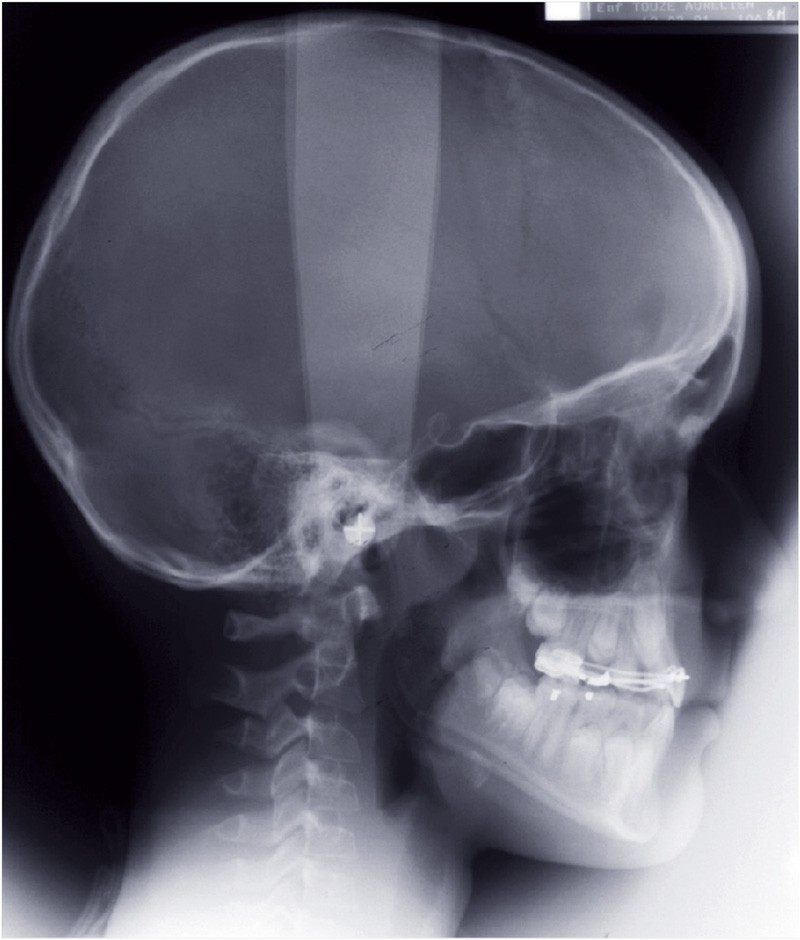

Le bilan radiographique (fig. 6) par l’analyse architecturale de Delaire et l’analyse dento-squelettique confirme l’examen clinique et conduit au diagnostic radiologique suivant :

• pas de prédisposition de la base du crâne à la classe III,

• rétromaxillie,

• brachymaxillie avec petite brachyprémaxillie,

• linguoversion incisive maxillaire,

• légère prognathie mandibulaire par dolichocorpie.